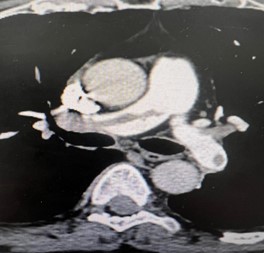

All patients were submitted to a preoperative pulmonary CT-SCAN, showing a large thrombus burden at main pulmonary arteries (figures 3 and 4).

Figure 4: CT-Scan demonstrating large thrombus burden at righ and left pulmonary artery